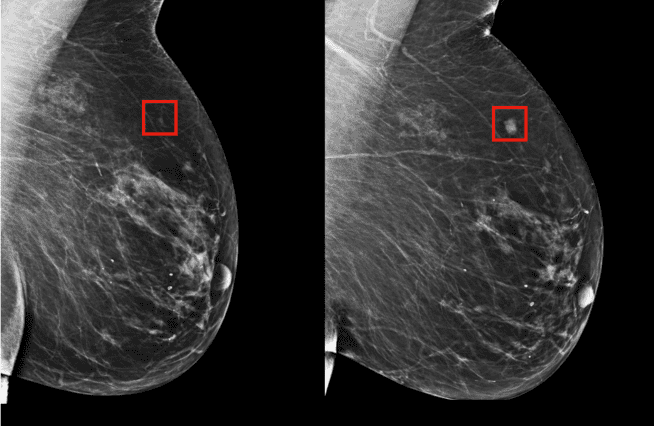

يعتمد هذا النموذج في عمله على تقنية التعلم العميق، حيث تمت تغذيته بحوالي 90,000 صورة للتصوير الإشعاعي للثدي تخص 60,000 مريض في مستشفى ماساتشوستس العام، مع النتائج المعروفة لهؤلاء المرضى بعد ذلك، فاستطاع النموذج أن يتعلم أنماطاً خفيةً في أنسجة الثدي اعتبرها مقدمةً لإصابته بالأورام الخبيثة.